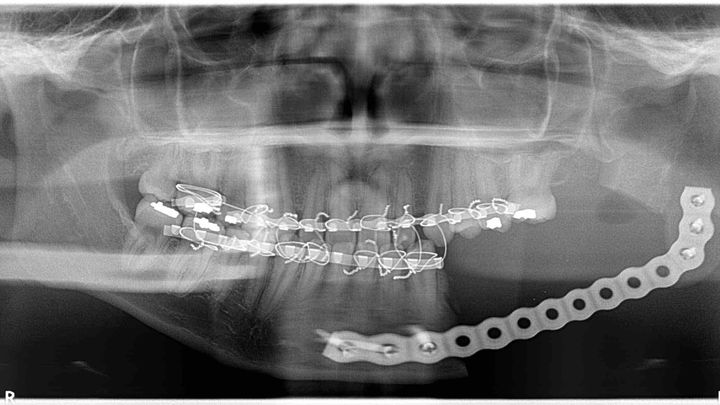

One year later in 2016, the cyst evolved into a tumor which could’ve become cancerous. This was the 3rd time I had to get surgery, and it would be the biggest one so far. The tumor killed 2 more of my teeth, leaving the lower left side of my jaw completely void of teeth. The tumor destroyed most of the bone in my jaw and left me with permanent nerve damage leaving part of my chin and lip completely numb. The surgeon also had to take part of my bone from my hip to transplant into my jaw along with a metal bar to help keep it’s shape, however, this wasn’t a permanent solution. A year went by, and one of the screws in the metal bar in my jaw came undone, which prompted yet another emergency surgery to add a whole new plate.

For the past 4 years, I’ve been unable to chew on the left side of my jaw due to all my missing teeth, I’ve felt pain only being able to chew on one side, my top left teeth are starting to come down, and all of this has severely affected my mental health and quality of life. As you can see in the photo I posted, the lower left side of my jaw is only held together with a metal bar which makes it extremely vulnerable and fragile. After going to countless doctors and traveling far and wide, I’ve learned that reconstructive surgery is my only option and the only place I can get this done is at UCLA. This surgery will involve taking even more bone from my right leg to place in my jaw and be able to get teeth implants. One of the things I love most in life is running and this surgery will weaken my leg, cause me to be bed ridden for 3 months, and will prevent me from running for over a year. Unfortunately, this solution will take an immense financial toll on both my mom and I and we can’t afford it. Our insurance barely helps and isn’t even accepted by 2 out of the 3 doctors who are going to be working on me, so most of the cost has to come out of our pockets. My doctor emphasized that this procedure is medically necessary or else I will have to face even more problems later in life.

One year later in 2016, the cyst evolved into a tumor which could’ve become cancerous. This was the 3rd time I had to get surgery, and it would be the biggest one so far. The tumor killed 2 more of my teeth, leaving the lower left side of my jaw completely void of teeth. The tumor destroyed most of the bone in my jaw and left me with permanent nerve damage leaving part of my chin and lip completely numb. The surgeon also had to take part of my bone from my hip to transplant into my jaw along with a metal bar to help keep it’s shape, however, this wasn’t a permanent solution. A year went by, and one of the screws in the metal bar in my jaw came undone, which prompted yet another emergency surgery to add a whole new plate.

For the past 4 years, I’ve been unable to chew on the left side of my jaw due to all my missing teeth, I’ve felt pain only being able to chew on one side, my top left teeth are starting to come down, and all of this has severely affected my mental health and quality of life. As you can see in the photo I posted, the lower left side of my jaw is only held together with a metal bar which makes it extremely vulnerable and fragile. After going to countless doctors and traveling far and wide, I’ve learned that reconstructive surgery is my only option and the only place I can get this done is at UCLA. This surgery will involve taking even more bone from my right leg to place in my jaw and be able to get teeth implants. One of the things I love most in life is running and this surgery will weaken my leg, cause me to be bed ridden for 3 months, and will prevent me from running for over a year. Unfortunately, this solution will take an immense financial toll on both my mom and I and we can’t afford it. Our insurance barely helps and isn’t even accepted by 2 out of the 3 doctors who are going to be working on me, so most of the cost has to come out of our pockets. My doctor emphasized that this procedure is medically necessary or else I will have to face even more problems later in life.